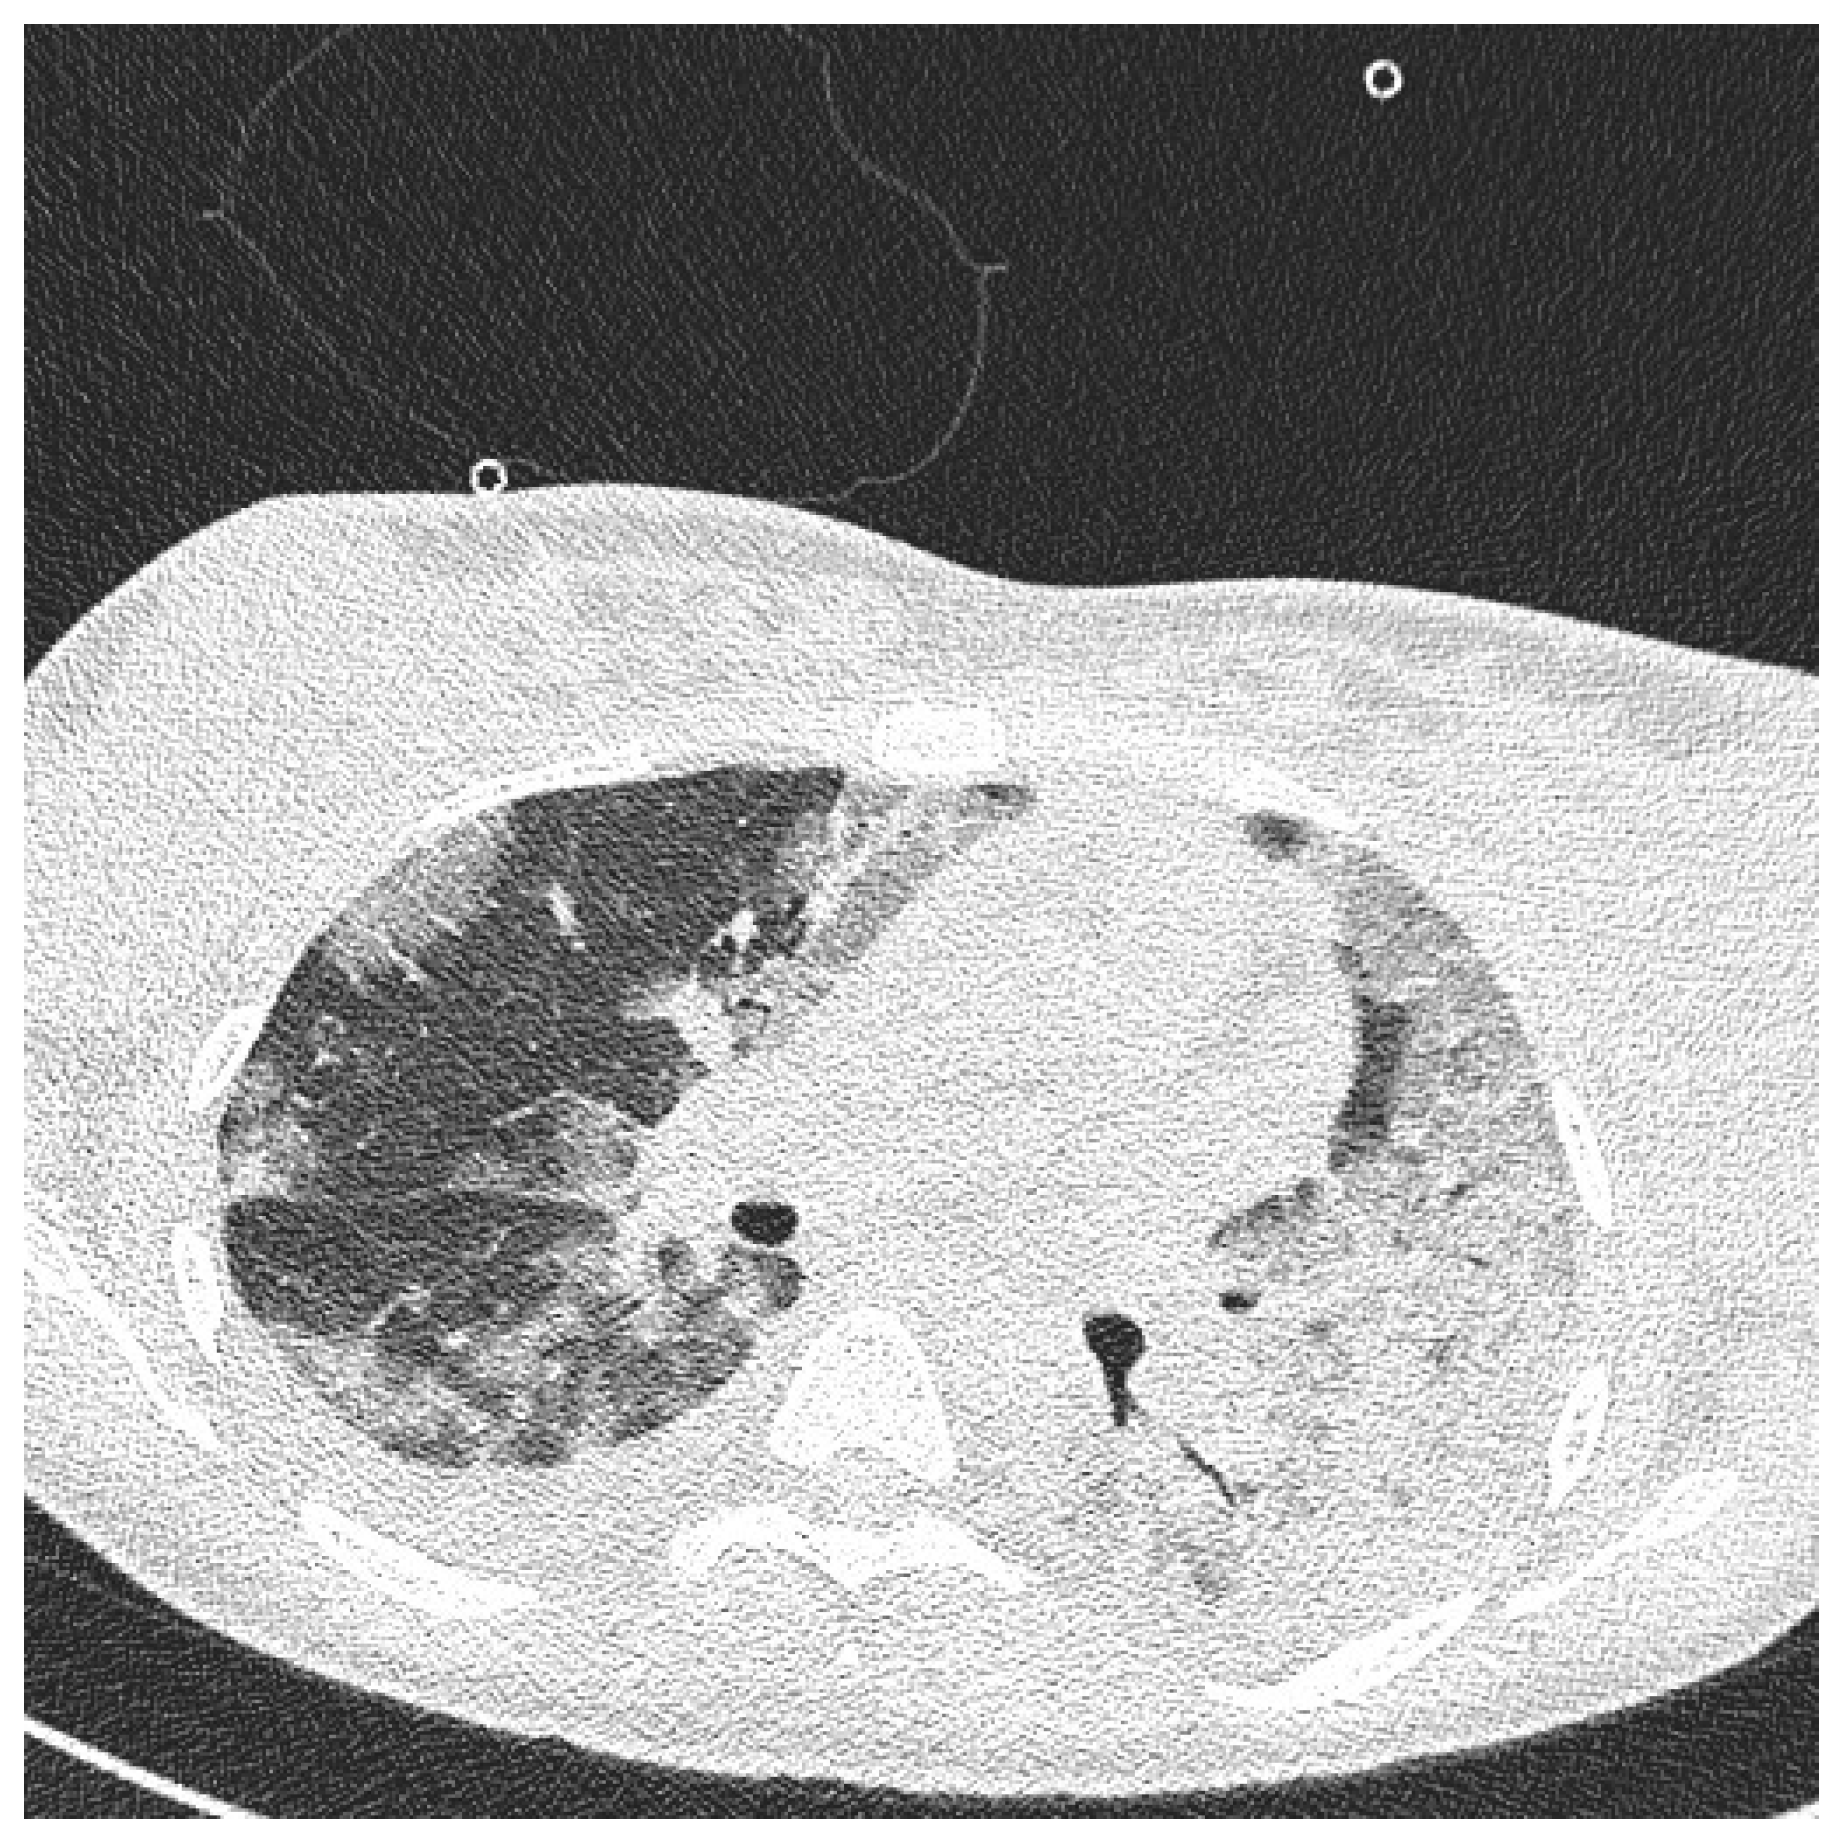

On the day of caesarean section, the patient’s vital parameters were: BP 130/80 mmHg, HR 110 bpm, Sat. 96%, breaths 20/min. Laboratory tests showed persistent abnormal clotting parameters. The drainage from the pelvis was 800 mL of blood, and in the control abdominal ultrasound examination the subcutaneous haematoma was observed. Due to the above, the patient was qualified to the relaparotomy and pelvic revision. During the procedure, another 2 g of fibrinogen, 2 units of platelet concentrate and 2 units of packed red blood cells were given. During the next two days, the patient was monitored in a postoperative room. Stable laboratory test values were obtained. Table 1 summarises the results of the patient’s examinations. A CT scan of the chest was performed. Massive converging zones of bubble densities in the type of frosted glass and paving stones, suggesting viral inflammation (typical for SARS-CoV-2 infection) were visible—see Figure 4 and Figure 5. Due to the gradually increasing respiratory failure (saturation 90%, and hypoxia—pO2 54 mmHg in a control arterial probe), high-flow nasal oxygen therapy was started. The satisfactory effect was not achieved. Sedation, intubation, and mechanical ventilation was initiated. After initial stabilisation the patient was transferred to the Intensive Care Unit, where she stayed for 8 days until improvement in oxygenation was achieved. She was successfully extubated and transferred to the Maternity Ward, from where she was discharged on the 22nd day of hospitalisation in good general condition.

Figure 4.

Chest Computed Tomography (HRCT).